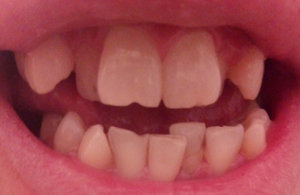

Мне 12 лет. У меня с 6-ти лет возникла такая проблема. Один из 2-х передних зубов стал расти на соседний зуб. Что мне поставят, скобы или брекеты?

Комментарий №177544

• Необходим осмотр и панорамный рентгеновский снимок зубов, оценка прикуса и соотношения зубов. В первую очередь следует лечить центральные резцы так как, по фото, они поражены кариесом. После проконсультируйтесь очно со стоматологом-ортодонтом для составления плана лечения. Скорее всего, в вашем возрасте чаще всего ставят пластины, а брекеты после 14 лет, когда полностью сфор читать далее